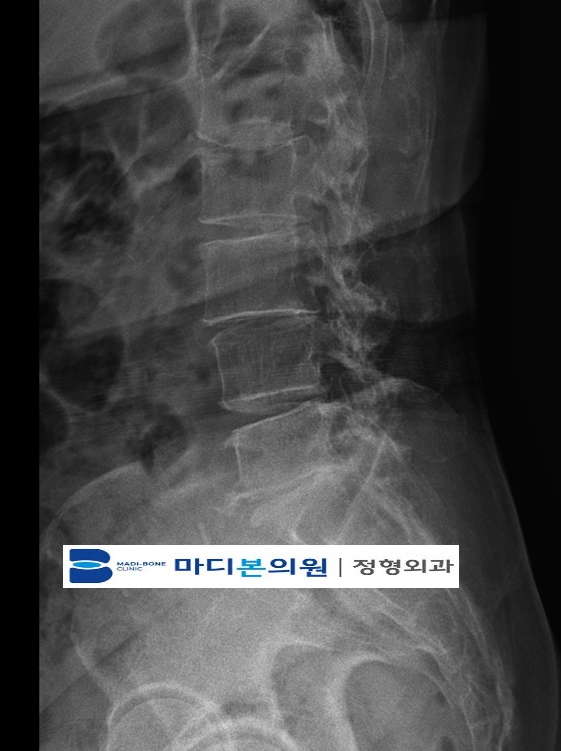

Disc Degeneration Is a Natural Part of Aging

Cervical and lumbar discs undergo degenerative changes as we age.

What Happens When a Disc Begins to Degenerate?

When disc aging begins, the disc loses hydration and elasticity.

Degeneration in the disc also increases the likelihood of:

- annular tears

- disc bulging

- herniation

- facet joint overload

Disc degeneration can disrupt the biomechanics of the spine, contributing to muscle strain and ligament injury.